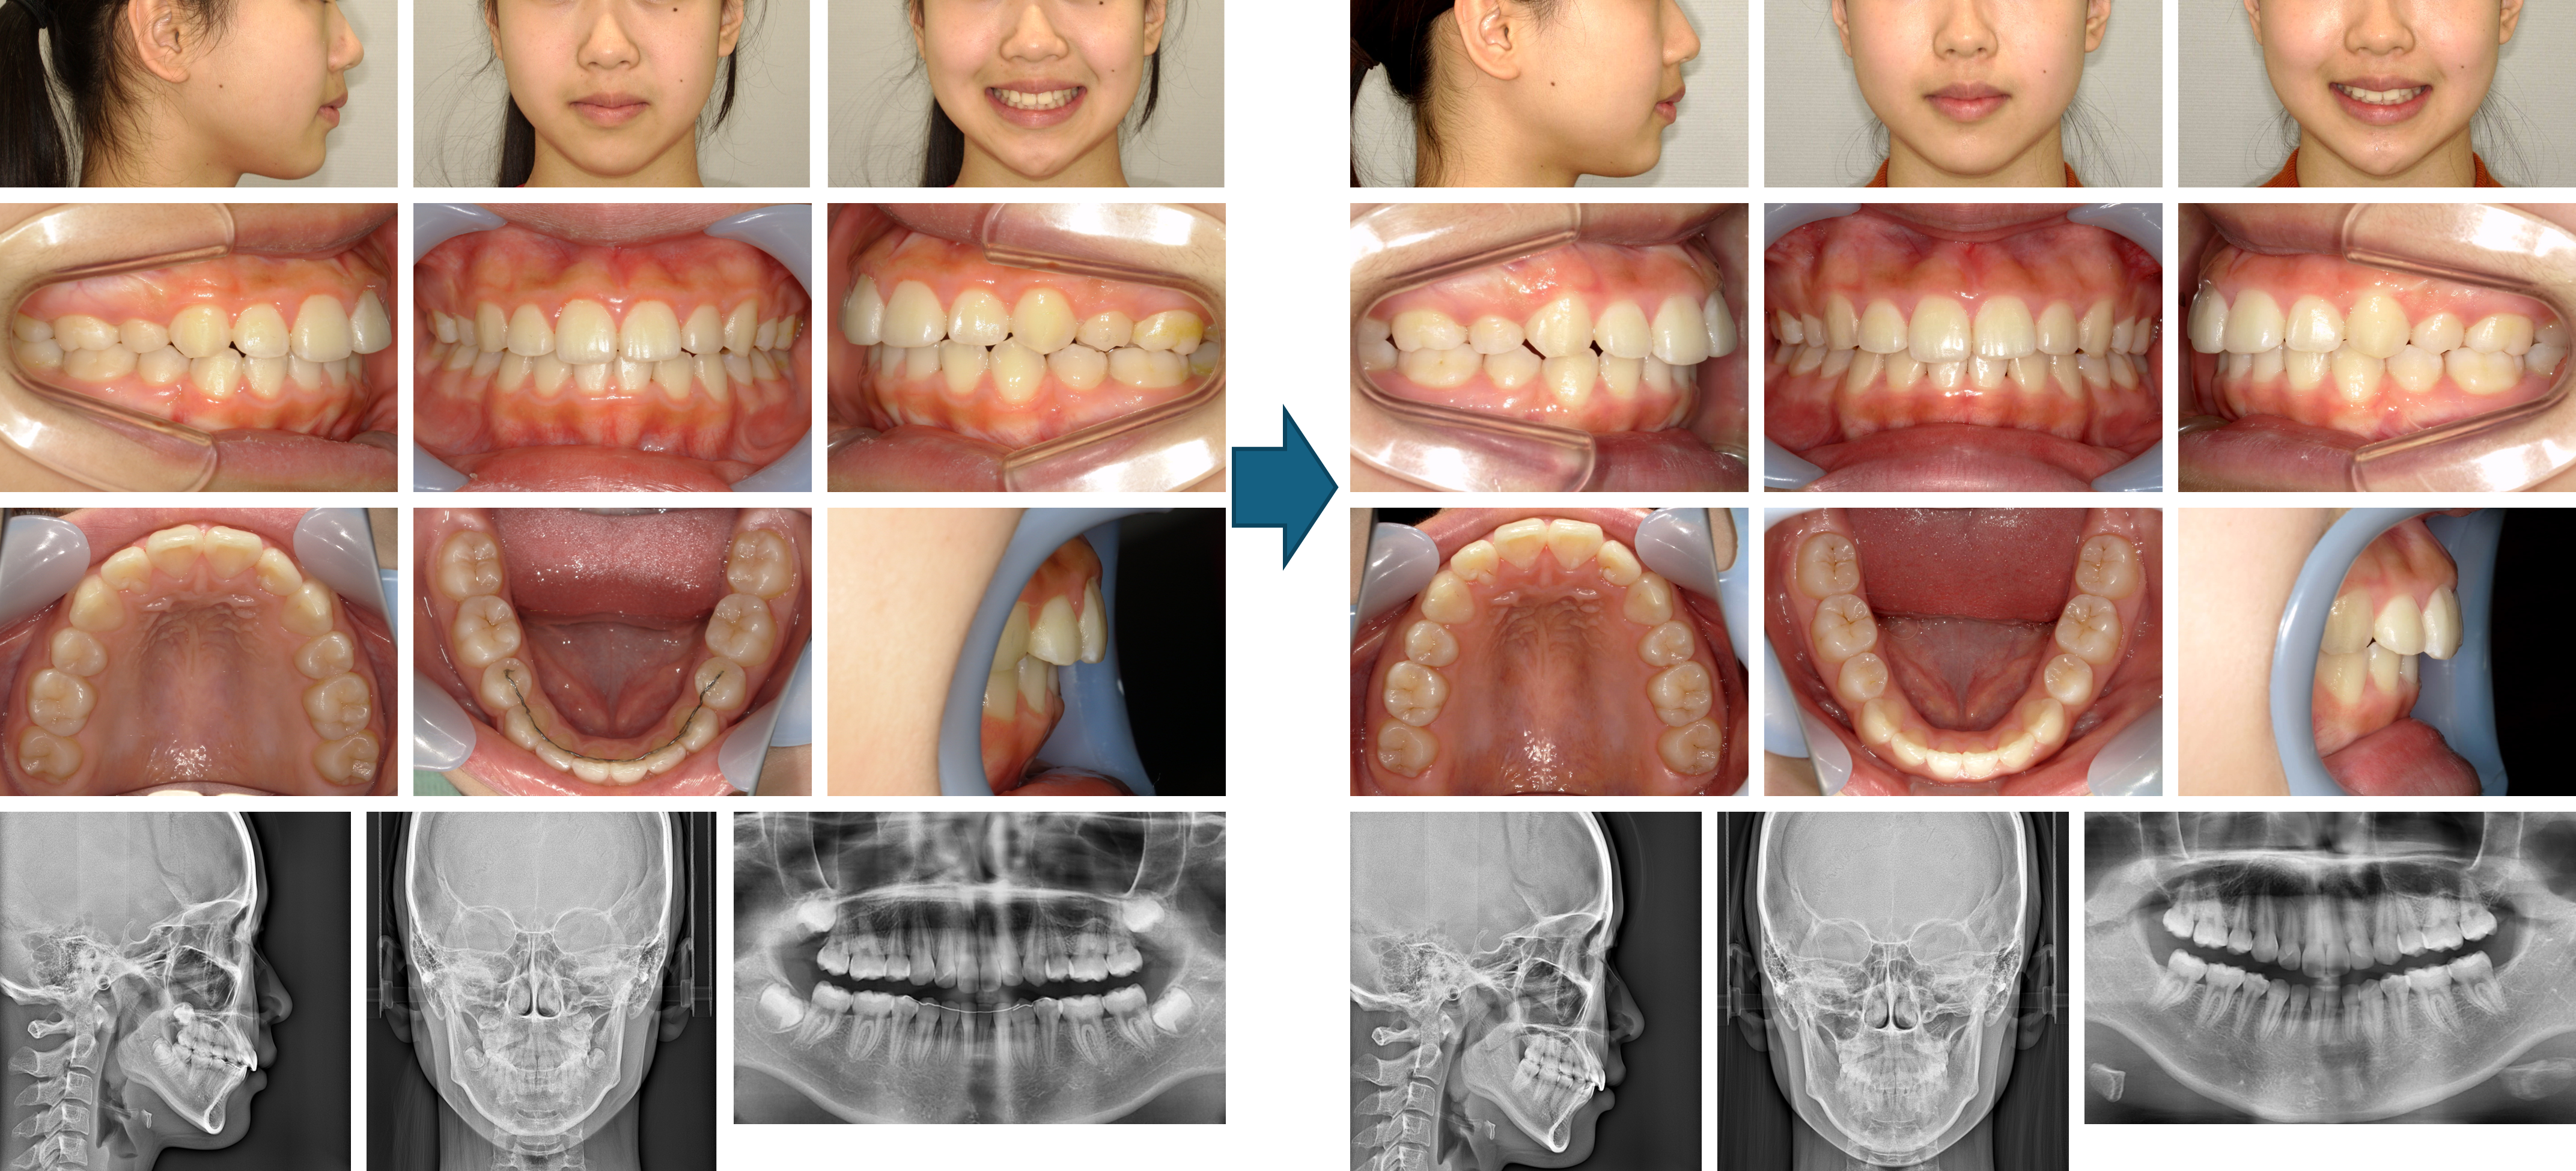

【治療例 K5284】初診時年齢:6歳11か月 / 性別:女性 / 主訴:前歯の咬み合わせ

治療の概要:第1期治療ではクワドヘリックスで側方拡大および右側中切歯の反対咬合の改善を行いながら、前方牽引装置で上顎骨の前方成長を促しました。2×4装置で上顎前歯部を綺麗に並べた後、しばらく永久歯の萌出を待ちました。側方歯の永久歯の萌出後、第2期治療では残りの永久歯にマルチブラケット装置を装着しました。綺麗な相貌と緊密な咬合を獲得しました。

主訴:前歯の咬み合わせ

診断名:上顎骨劣成長を伴う骨格性Ⅲ級、右側中切歯の反対咬合

使用した主な装置:クワドヘリックス、フェイスマスク、マルチブラケット装置、顎間ゴム

抜歯/非抜歯および抜歯部位: 非抜歯(ただし、乳歯の抜歯はあり)

治療期間:5年8か月(第1期治療:2年1か月、 第2期治療:3年7か月)

治療回数:第1期治療13回、第2期治療61回

【治療例 K6639】初診時年齢:8歳5か月 / 性別:女性 / 主訴:上前歯がゆがんで生えている。

治療の概要:右上1番の反対咬合を主訴に来院した。上顎にリンガルアーチで被蓋の改善を行った後、上顎4前歯のみセクショナルワイヤーを装着し歯列を整えた後、乳歯から永久歯への咬合誘導のみで終了した症例。

主訴:上前歯がゆがんで生えている。

診断名:前歯部反対咬合を認める混合歯列期前期の叢生症例

使用した主な装置:リンガルアーチ、上顎前歯部のみのマルチブラケット装置

抜歯/非抜歯および抜歯部位:非抜歯

治療期間:5年6か月

治療回数:33回